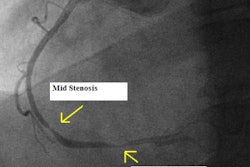

Post-transplant monitoring is needed to keep tabs on intimal proliferation, which can lead to severe coronary artery stenosis, and may be responsible for as many as 40% of the late deaths among heart transplant patients.

Radiologists at Diagnóstico Maipu in Buenos Aires found that CT compared favorably to IVUS and angiography. In fact, conventional angiography often misses the problem entirely, the team reports in today's Insider Exclusive story, published for Insider subscribers before it's made available to other members.